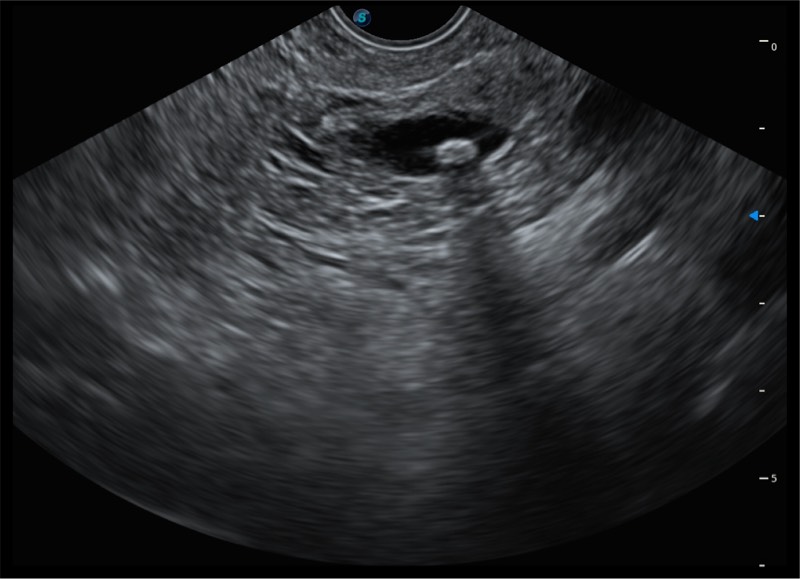

基于二十年的超声技术积累,乐玩lewin国际提供了最新一代的独立超声主机,在提供高质量图像的同时满足多学科使用。具备常见多普勒技术并提供弹性成像、声学造影等高端影像技术。新一代传感器具有更强的抗干扰能力并减少图像伪影。

150°超声扫描角度